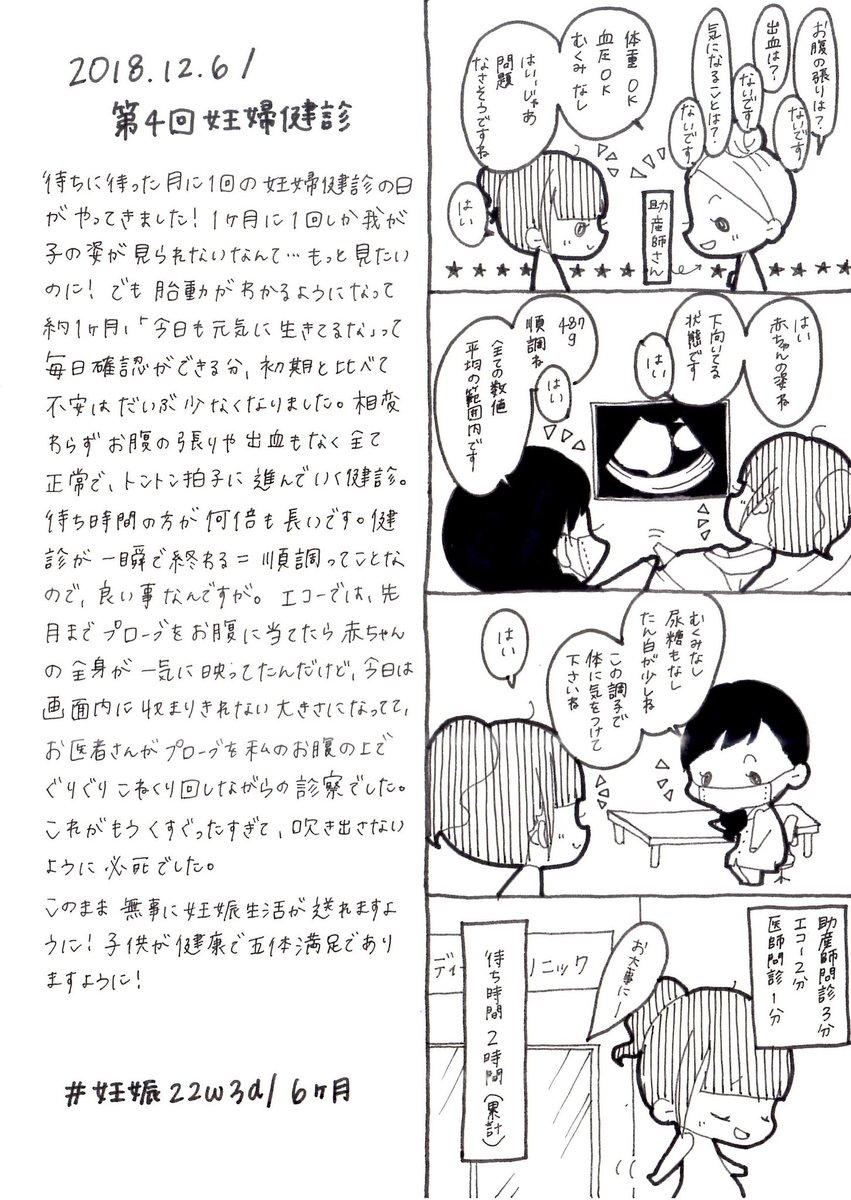

2018.12.6 第4回妊婦健診! なーんにも問題がなく健診自体は超絶スムーズ…だけど、待ち時間が長いよね、いつも…。 エコーとお腹の写真載せます、閲覧注意! #育児漫画 #育児日記 #妊娠 #妊娠中期 #妊婦健診 #エコー #妊娠6ヶ月 #イラスト好きさんと繋がりたい #オリジナル漫画 pic.twitter.com/8NX8J1yy9T

拡大

拡大

拡大

拡大

拡大